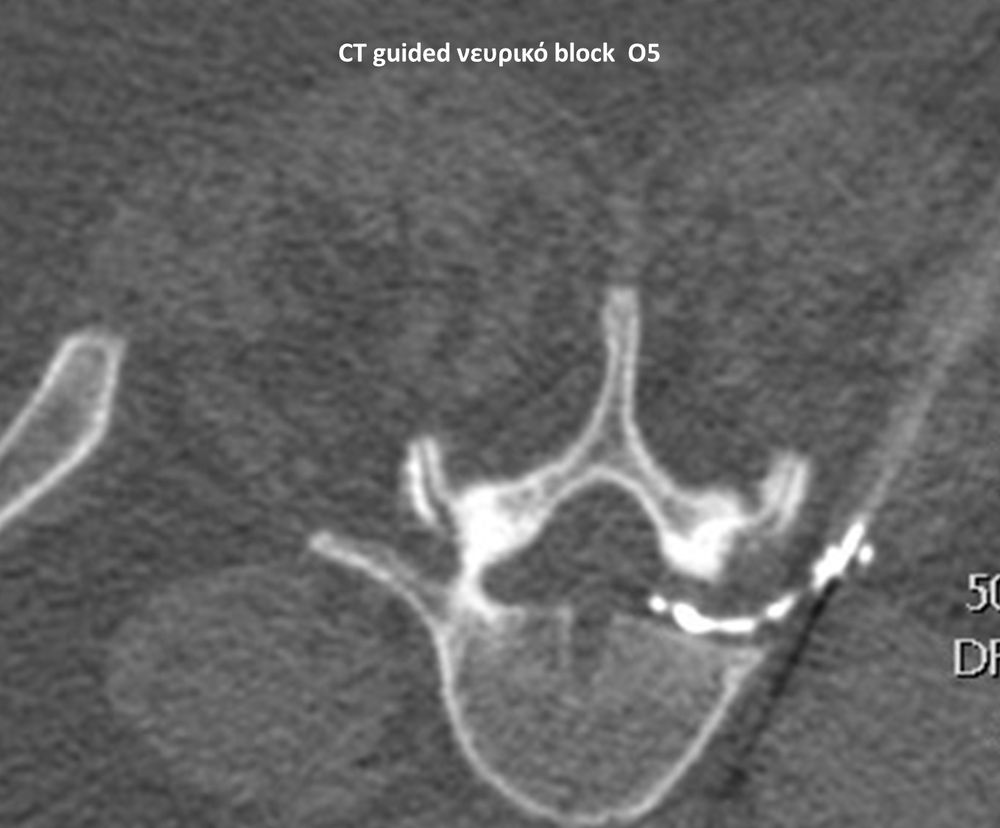

Με την βοήθεια της επεμβατικής ακτινολογίας είναι δυνατόν να πραγματοποιηθούν διαφορες ενέσιμες τεχνικές που αποσκοπούν στη μείωση του μυοσκελετικού πόνου, την ενίσχυση της αποτελεσματικότητας της φυσιοθεραπείας και την επιτάχυνση της διαδικασίας επούλωσης. Οι τεχνικές αυτές περιλαμβάνουν την κατευθυνόμενη έγχυση φαρμάκων ή πραγματοποίηση θεραπευτικών χειρισμών ακριβώς στη θέση τηςπαθολογία. Ετσι εξασφαλιζεται η μέγιστη αποτελεσματικότητα ( έως 95% κατά περίπτωση) και ασφάλεια σε σχέση με τυφλούς χειρισμούς χωρίς ακτινολογική καθοδήγηση.